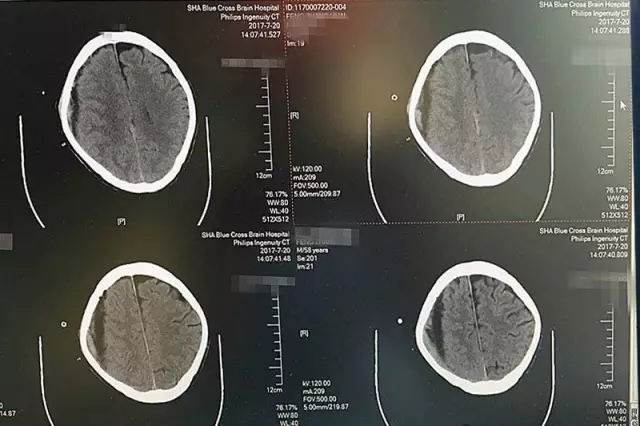

紅圈處為高密度引流管,進(jìn)入顱內(nèi)約1.2厘米,后部為放射狀偽影

患者術(shù)后CT影像顯示:血腫基本被吸收

第一天,術(shù)中引流出暗紅色血液120毫升左右,腦CT影像顯示,血腫大部分被吸收。

第二天,又引流出90毫升暗紅色血液,術(shù)后CT顯示血腫基本清除干凈。

第三天,血腫順利被清除,就像工兵搬走了地雷,警報(bào)解除。